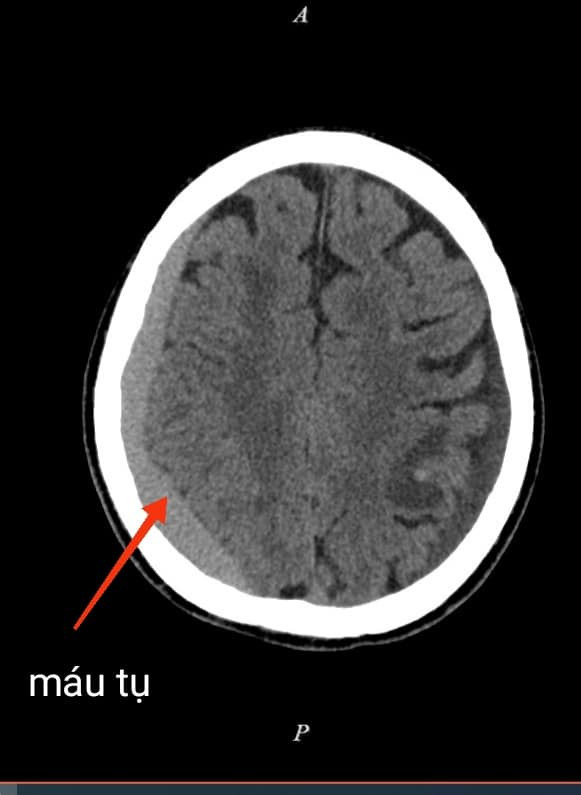

Trường hợp bệnh nhân nam 68 tuổi, sau tai nạn giao thông khoảng 2 tháng trước, bệnh nhân xuất hiện đau đầu âm ỉ tăng dần, có cơn co giật, đi khám chụp cắt lớp vi tính sọ não phát hiện tụ máu dưới màng cứng mạn tính bán cầu bên phải, có chỉ định phẫu thuật.

| Hình ảnh chụp cắt lớp vi tính của bệnh nhân trước và sau phẫu thuật |

Ngày nay chẩn đoán xác định máu tụ dưới màng cứng mạn tính bằng máy chụp Cắt lớp vi tính và máy chụp Cộng hưởng từ cho kết quả chính xác cao, hiện đã có ở nhiều địa phương, rất thuận tiện cho chẩn đoán.